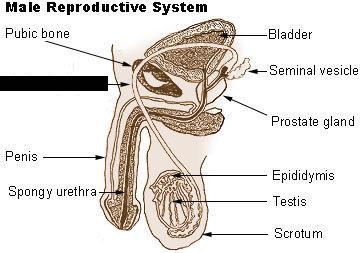

Corpora cavernosa (pl.) Corpus Cavernosum (s.)

Corpus Spongiosum

Cremaster muscle

Ejaculatory Duct

Epididymis

External urethral orifice (male)

Glans penis

Prostate gland

Prostatic/spongy urethra (males)

Scrotum

Seminal vesicle

Seminiferous tubule

Spermatic cord

Testis (s.) Testes (pl.)

Vas deferens (=ductus deferens)